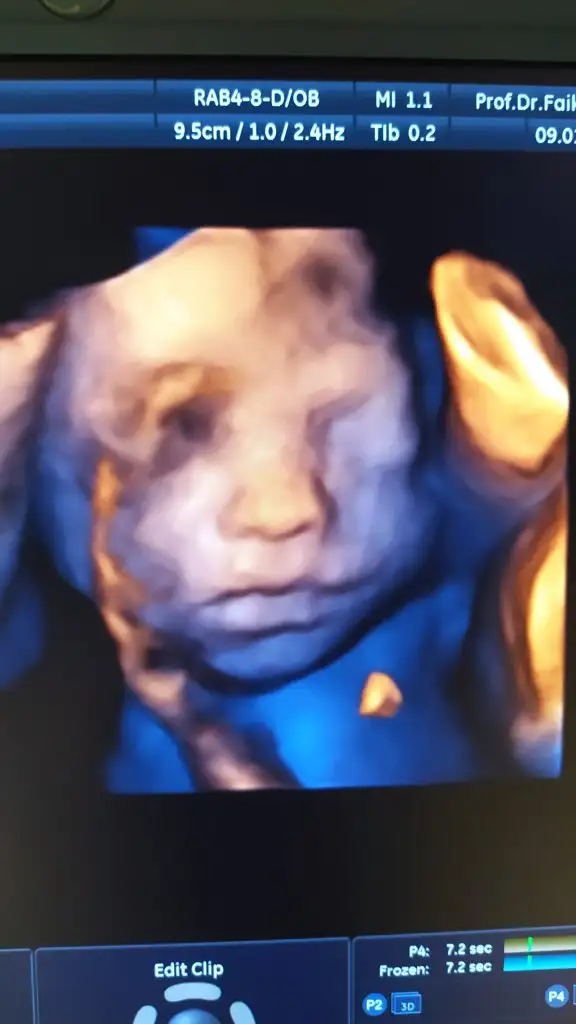

Senin ağzını burnunu yerim maasallah kuzumm ay keske siz dogursanizda ben sevsem yakınım da olsanizSelam herkese. Bizim de bugün kontrolümüz vardı 25+2 deyiz 800 gram olmuş oğluş boyunu sordum onu bilemeyiz dedi doktorbu hafta içi de gidip şeker yükleme testi yaptırıcam zayıfsın ama zayıflarda da çıkabiliyor şeker o yüzden yaptır dedi dr. Güzel bir haftasonu olsun fotoğrafımızı da ekleyeyim

Fl değeri yazıyo mu kâğıtlarda cnm o değeri 7yle çarp boyu cikiyoSelam herkese. Bizim de bugün kontrolümüz vardı 25+2 deyiz 800 gram olmuş oğluş boyunu sordum onu bilemeyiz dedi doktorbu hafta içi de gidip şeker yükleme testi yaptırıcam zayıfsın ama zayıflarda da çıkabiliyor şeker o yüzden yaptır dedi dr. Güzel bir haftasonu olsun fotoğrafımızı da ekleyeyim

Allah allah neden bilemiyomuş boyunu :/ bende dün gittim 25+3 düm 33 cm dedi boyunaSelam herkese. Bizim de bugün kontrolümüz vardı 25+2 deyiz 800 gram olmuş oğluş boyunu sordum onu bilemeyiz dedi doktorbu hafta içi de gidip şeker yükleme testi yaptırıcam zayıfsın ama zayıflarda da çıkabiliyor şeker o yüzden yaptır dedi dr. Güzel bir haftasonu olsun fotoğrafımızı da ekleyeyim

Maşallah yavruyaSelam herkese. Bizim de bugün kontrolümüz vardı 25+2 deyiz 800 gram olmuş oğluş boyunu sordum onu bilemeyiz dedi doktorbu hafta içi de gidip şeker yükleme testi yaptırıcam zayıfsın ama zayıflarda da çıkabiliyor şeker o yüzden yaptır dedi dr. Güzel bir haftasonu olsun fotoğrafımızı da ekleyeyim

Teşekkür ederiz teyzesiFl değeri yazıyo mu kâğıtlarda cnm o değeri 7yle çarp boyu cikiyomaşallah çok tatlı bisey

Canım benim çok sağol, tüm bebişler çok güzelllMaşallah yavruyaAllahım özene bözene yaratıyor vallahi öyle güzeller ki insan bakmaya kıyamıyor nazar değmesin Maşallah oğluşun sana tam öncesi sonrası yapmalık poz vermiş annesi